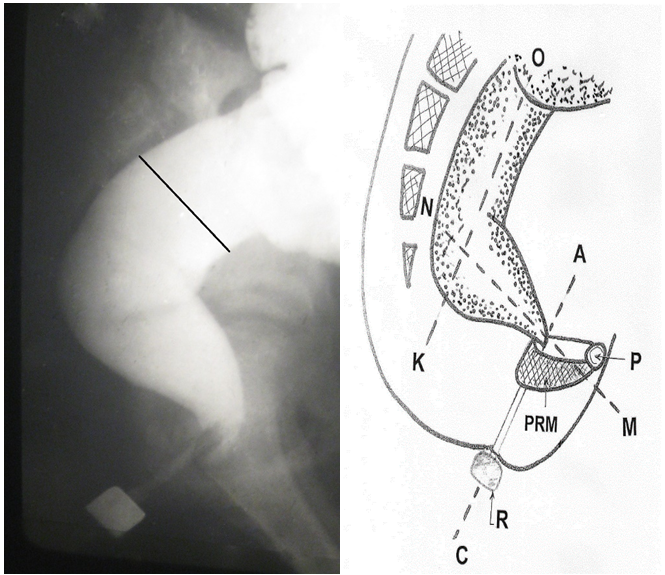

The study was conducted by the hydrostatic barium enema.7,8 Only in infants up to 3 months the bowel filling was made from a rubber bulb. In other cases, a barium was introduced from the graduated bag. The bottom of this bag at the beginning of the study was located 40 cm above the deck of the table. A barium was introduced into the colon up to the reflux into the terminal ileum. The difference of barium volume in the bag before and after the colon filling corresponds to the colon volume. The radiopaque marker is strung on the tip of the enema. It is in contact with the anus during the study. At least two radiographs (frontal and lateral) have been made after the filling of the colon. On a frontal radiograph the widths of the different parts of the colon are measured (Figure 1). Since the rectum forms two bends in two projections, it cannot be differentiated on the frontal radiograph, which makes it impossible to measure its width. On a lateral radiograph were measured the maximum width of the vertical portion of the rectum, as well as interval not containing contrast medium between the rectum and a contrast marker on the posterior contour of the tip (Figure 2).

Figure 1 Frontal colonography and scheme to it.

The locations of the measurements of the different parts of the colon are marked: (a) the height of the cecum; widest part of each section were measured: (b) cecum, (c) ascending colon, (d) transverse colon (e) descending colon, (f) sigmoid colon.